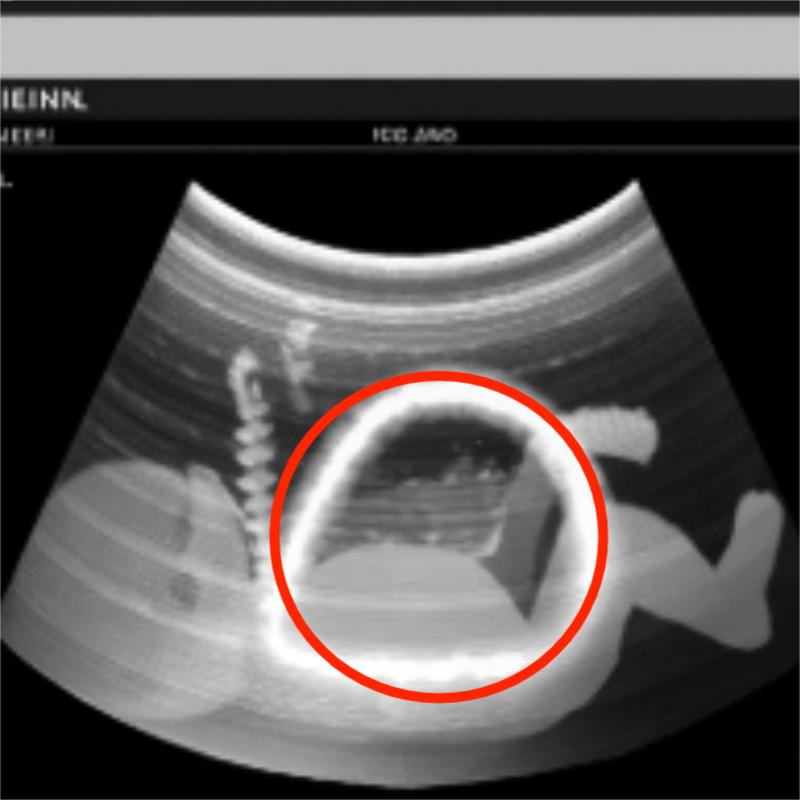

We saw our baby before we ever heard his cry. The room was dim and still, filled with the gentle rhythm of machines—soft beeps and quiet whirs that marked time in a language we were just beginning to understand. On the screen, the image appeared in pieces: the spine first, a delicate string of white pearls curving gracefully—until it didn’t. A small darkness opened where light should have been, a break in the song of bone. My breath caught, and David’s cold hand found mine. His fingers trembled, as if holding on was the only thing keeping us both steady.

The sonographer slowed her movements, measuring carefully, tracing circles around that dark space—a dotted outline that looked too much like a target. I couldn’t stop staring at it. I had one foolish thought: if I could reach through the screen and touch it, maybe it would close.

When the doctor came in, his calm voice was the only thing holding the room together. “We’re seeing a discontinuity,” he said gently, “perhaps a lesion near the lower spine. Sometimes it’s treatable. We’ll take this step by step.” His lips moved on, but all I could hear was the watery drumbeat of our baby’s heart.